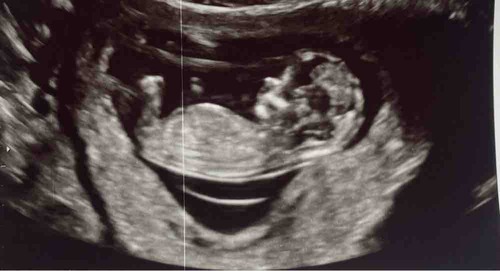

Blauw: omranding

Rood: Blaas

Groen: stand nub en blaas met ruggengraad

Zoals je kan zien in de ingezoomde echos met alleen blauw zie je een klein bolletje/boven de nub lijn. Dit is normaal het begin van de ontwikkeling van de pipi

De lijn van de nub veranderd dan in de balletjes.

Zoals op de echo met de andere kleuren lijnen is er meer schaduw bij gedaan waardoor je ook duidelijker ziet dat de nub omhoog staat. De blaas zit ook erg laag en van nub naar blaas naar ruggengraad staat het in een hoek naar de ruggengraad(📐) dit duidt op een jongen. Bij meisjes loopt het gelijk of bijna gelijk aan de ruggengraad(=) de blaas zit daar dichter tegen de nub aan en is de nub plat en is er geen bolletje.

Dus ik gok jongen